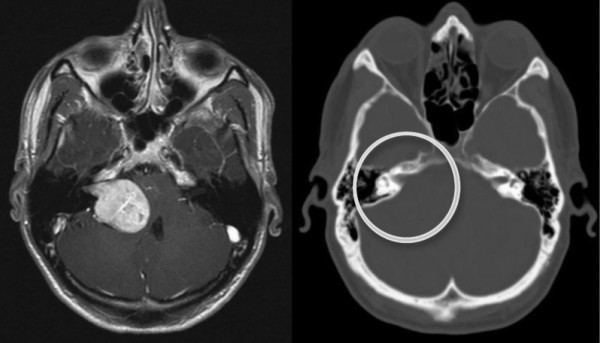

- исследование с использованием компьютерной томографии (КТ) и магнитно-резонансной томографии (МРТ);

Магнитно-резонансная томография (МРТ) является одним из методов выявления невриномы

Диагностика невриномы слухового нерва включает проведение аудиометрии, магнитно-резонансной томографии (МРТ) и компьютерной томографии (КТ) для определения размера и местоположения опухоли.